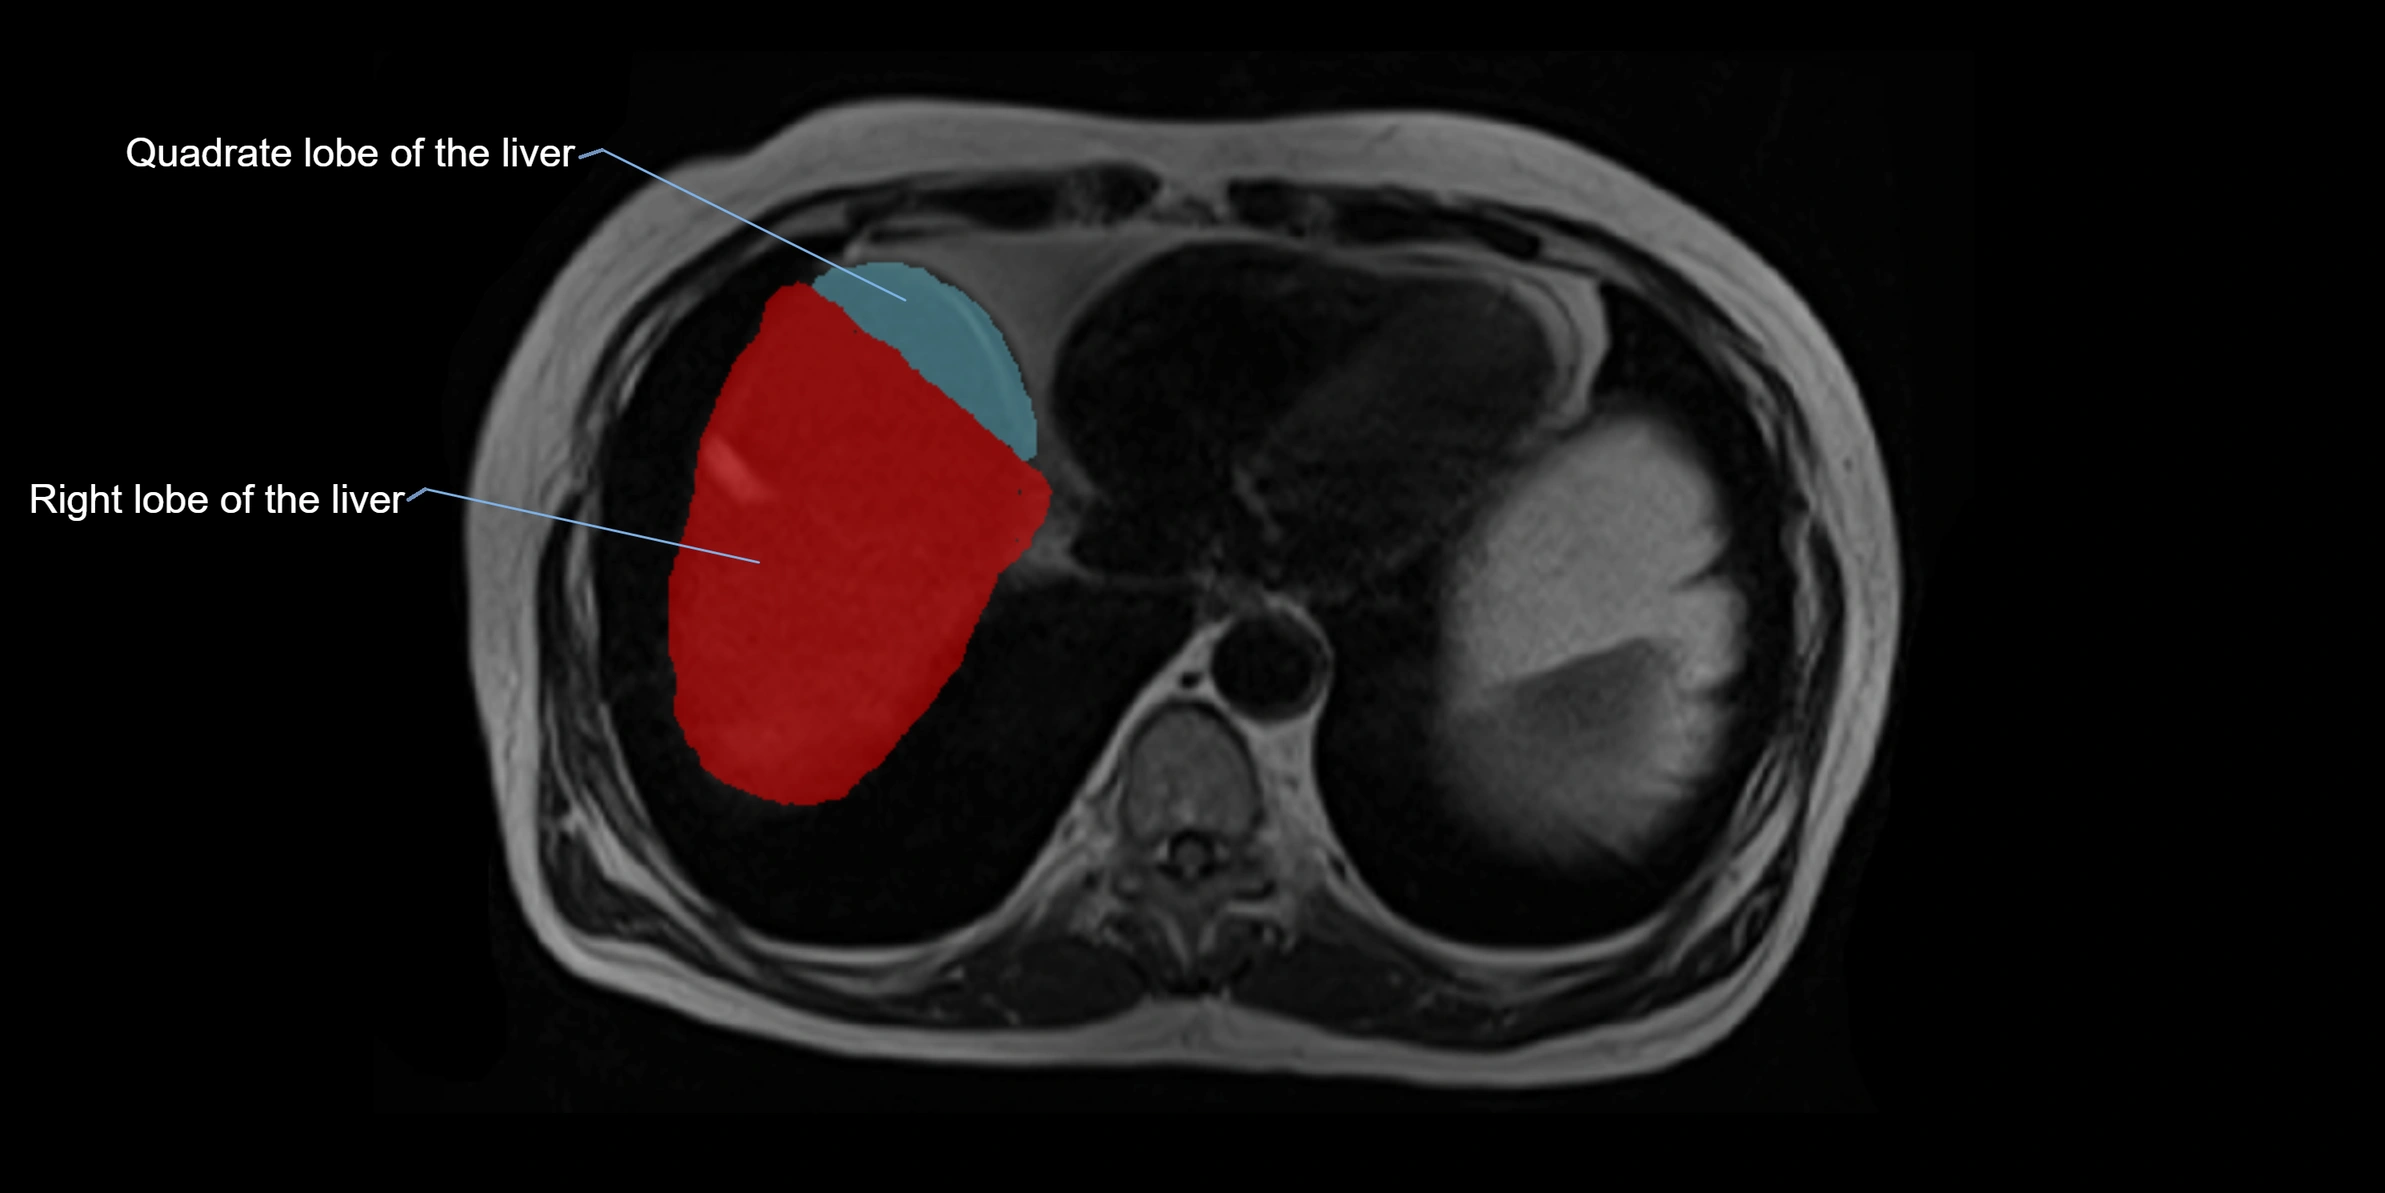

The caudate lobe of the liver is a distinct anatomical subdivision of the liver, designated as segment I in Couinaud’s classification. It lies on the posterior surface of the liver, between the fissure for the ligamentum venosum (left boundary) and the groove for the inferior vena cava (IVC) (right boundary). Superiorly, it is related to the posterior liver surface, and inferiorly it is separated from the left lobe by the porta hepatis.